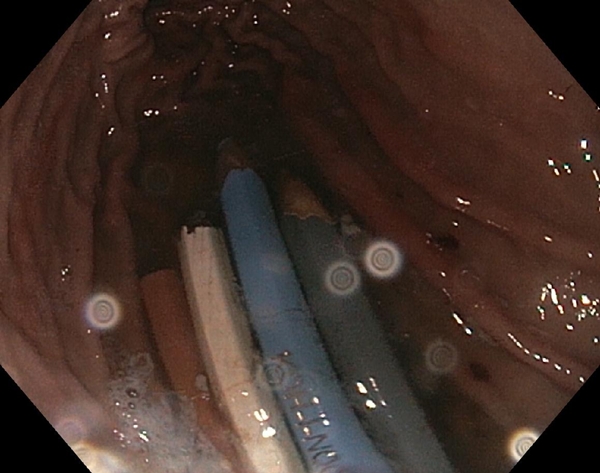

Větší množství pastelek. Tentokrát jsem kromě výsledného přehledu udělal i několik fotek zevnitř žaludku. Tahat pastelky není až tak těžké, bohužel jejich počet zákrok značně protáhl...